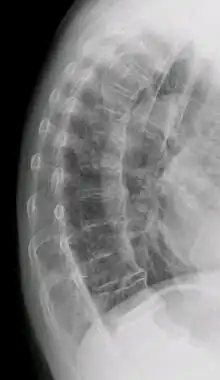

DISH in an 80 year old female, also with T11 fracture.

DISH is diagnosed by findings on x-ray studies. Radiographs of the spine will show abnormal bone formation (ossification) along the anterior spinal ligament. The disc spaces, facet and sacroiliac joints remain unaffected. Diagnosis requires confluent ossification of at least four contiguous vertebral bodies.[2] Classically, advanced disease may have "melted candle wax" appearance along the spine on radiographic studies.[13] In some cases, DISH may be manifested as ossification, or enthesis, in other parts of the skeleton.